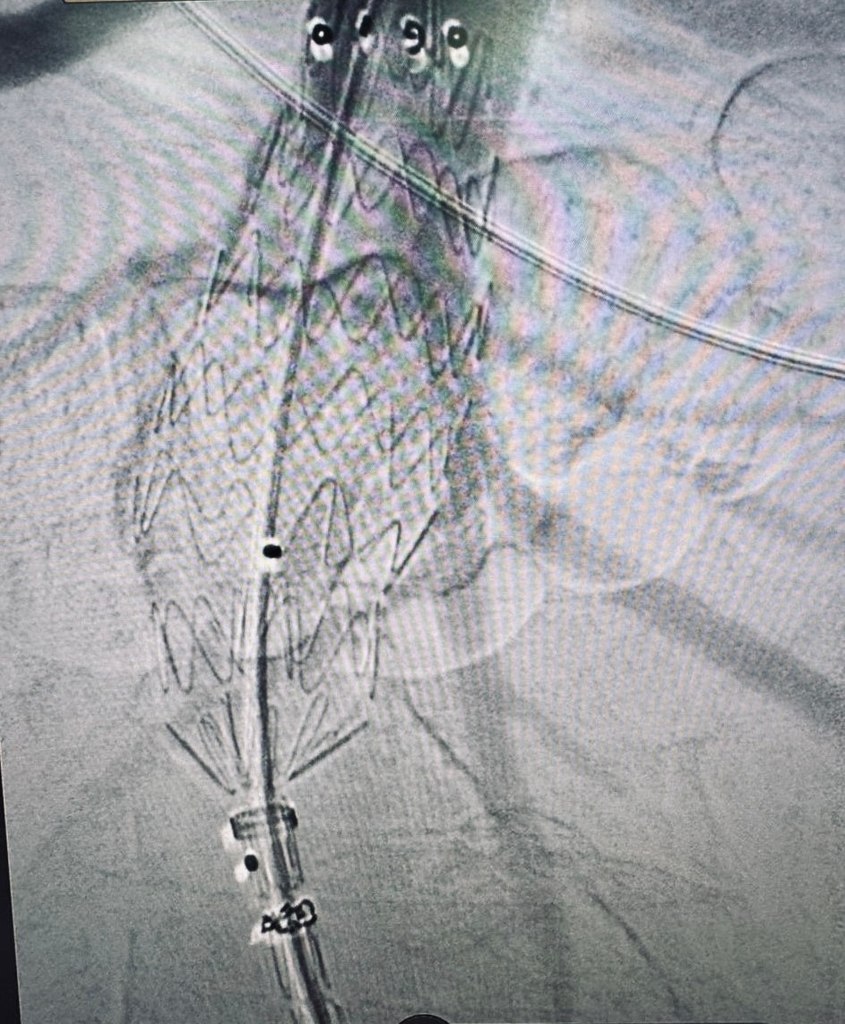

В Региональном сосудистом центре Областной больницы впервые выполнено эндопротезирование брюшной аорты.

Эндопротезирование брюшного отдела аорты — это инновационная малотравматичная методика, которая позволяет:

Операция выполнена руководителем центра Андреем Куликовым, заведующим отделением сосудистой хирургии Игорем Гладковым, заведующим отделением рентгенхирургических методов лечения и диагностики Андреем Колуновым и врачами отделения сосудистой хирургии.